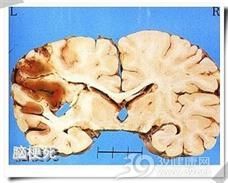

腦梗塞又稱缺血性腦卒中(cerebral ischemic stroke),是指因腦部血液供應(yīng)障礙,缺血、缺氧所導(dǎo)致的局限性腦組織的缺血性壞死或軟化。腦梗塞的臨床常見類型有腦血栓形成、腔隙性梗死和腦栓塞等,腦梗塞占全部腦卒中的80%。與其關(guān)系密切的疾病有:糖尿病、肥胖、高血壓、風(fēng)濕性心臟病、心律失常、各種原因的脫水、各種動脈炎、休克、血壓下降過快過大等。臨床表現(xiàn)以猝然昏倒、不省人事、半身不遂、言語障礙、智力障礙為主要特征。腦梗塞不僅給人類健康和生命造成極大威脅,而且給患者、家庭及社會帶來極大的痛苦和沉重的負(fù)擔(dān)。填寫父親健康狀況,就寫腦梗塞就可以了。

腦梗死(cerebralinfarction,CI)是缺血性卒中(ischemic stroke)的總稱,包括腦血栓形成、腔隙性梗死和腦栓塞等,約占全部腦卒中的70%,是腦血液供應(yīng)障礙引起腦部病變。腦梗死是由于腦組織局部供血動脈血流的突然減少或停止,造成該血管供血區(qū)的腦組織缺血、缺氧導(dǎo)致腦組織壞死、軟化,并伴有相應(yīng)部位的臨床癥狀和體征,如偏癱、失語等神經(jīng)功能缺失的癥候。腦梗死發(fā)病24~48h后,腦CT掃描可見相應(yīng)部位的低密度灶,邊界欠清晰,可有一定的占位效應(yīng)。腦MRI檢查能較早期發(fā)現(xiàn)腦梗死,表現(xiàn)為加權(quán)圖像上T1在病灶區(qū)呈低信號,T2呈高信號,MRI能發(fā)現(xiàn)較小的梗死病灶。